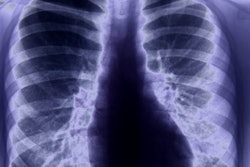

The ACR National Clinical Imaging Research Registry (ANCIRR) currently includes six image databases, with eight more to come, the college said. Images come from a variety of practice settings and give researchers access to large datasets.

The newest registry of the first six is a COVID-19 database that serves as the primary data collection for the National Institute of Biomedical Imaging and Bioengineering (NIBIB)-funded Medical Imaging and Data Resource Center (MIDRC). This set also provides images to the Society of Critical Care Medicine VIRUS COVID-19 Registry and the National Heart, Lung and Blood Institute PETAL Clinical Trials Network, the ACR said.